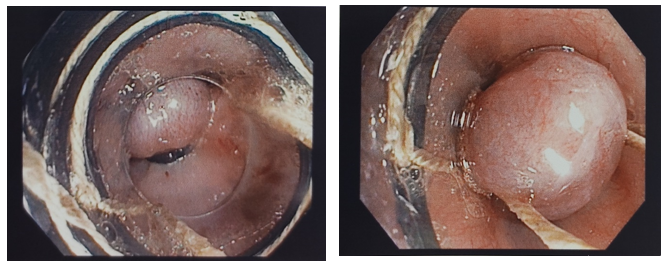

The handle was then turned clockwise to deploy the band. Bands were placed along the esophagus in ascending order (Figure 1 demonstrates the procedure).12 EVL treatments were arranged at monthly intervals until the varices were either destroyed or diminished to Grade I or tiny thrombosed varices deemed unsuitable for ligation. A maximum of four bands were applied per session, starting in the distal esophagus, utilizing the multiband ligation device (Six Shooter). Endoscopies were performed monthly or sooner in the event of upper gastrointestinal bleeding, maintained for a minimum of one year. Band ligation, oral propranolol, and Omeprazole 1 mg/kg/day were given to all patients for at least two months or until endoscopic reassessment.14 Variceal grading, the number of band ligation sessions, the number of bands per session, full variceal obliteration, the incidence of early and late re-bleeding, and any complications were used to assess the effectiveness of the treatment (Figure 2).8

Figure 3 Endoscopic image showing large esophageal varix & ligating the varix using multiband ligator.